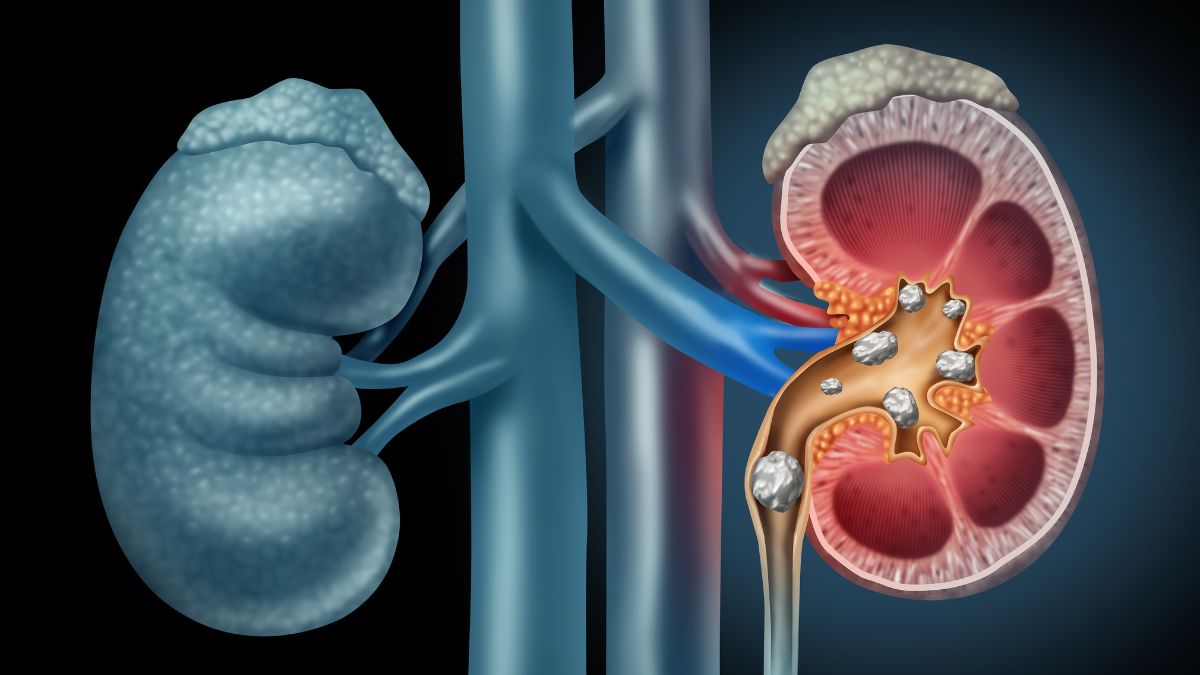

Kidney கற்கள் உங்கள் சிறுநீரகங்களுக்குள் உருவாகின்றன மற்றும் உங்கள் சிறுநீர் பாதையின் எந்தப் பகுதியையும் பாதிக்கலாம். குமட்டல், வாந்தி, காய்ச்சல், சிறுநீரில் இரத்தம் மற்றும் அடிக்கடி சிறுநீர் கழித்தல் ஆகியவற்றுடன் கீழ் முதுகு, வயிறு அல்லது பக்கவாட்டில் கடுமையான வலியை ஏற்படுத்தக்கூடிய வலிமிகுந்த நிலை இது.